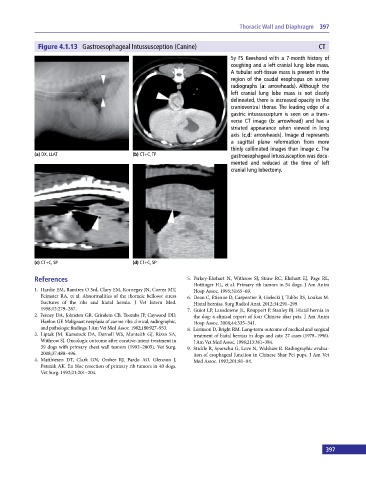

Figure 4.1.13 Gastroesophageal Intussusception (Canine) CT

5y FS Keeshond with a 7‐month history of

coughing and a left cranial lung lobe mass.

A tubular soft‐tissue mass is present in the

region of the caudal esophagus on survey

radiographs (a: arrowheads). Although the

left cranial lung lobe mass is not clearly

delineated, there is increased opacity in the

cranioventral thorax. The leading edge of a

gastric intussusceptum is seen on a trans-

verse CT image (b: arrowhead) and has a

striated appearance when viewed in long

axis (c,d: arrowheads). Image d represents

a sagittal plane reformation from more

thinly collimated images than image c. The

(a) DX, LLAT (b) CT+C, TP gastroesophageal intussusception was docu-

mented and reduced at the time of left

cranial lung lobectomy.